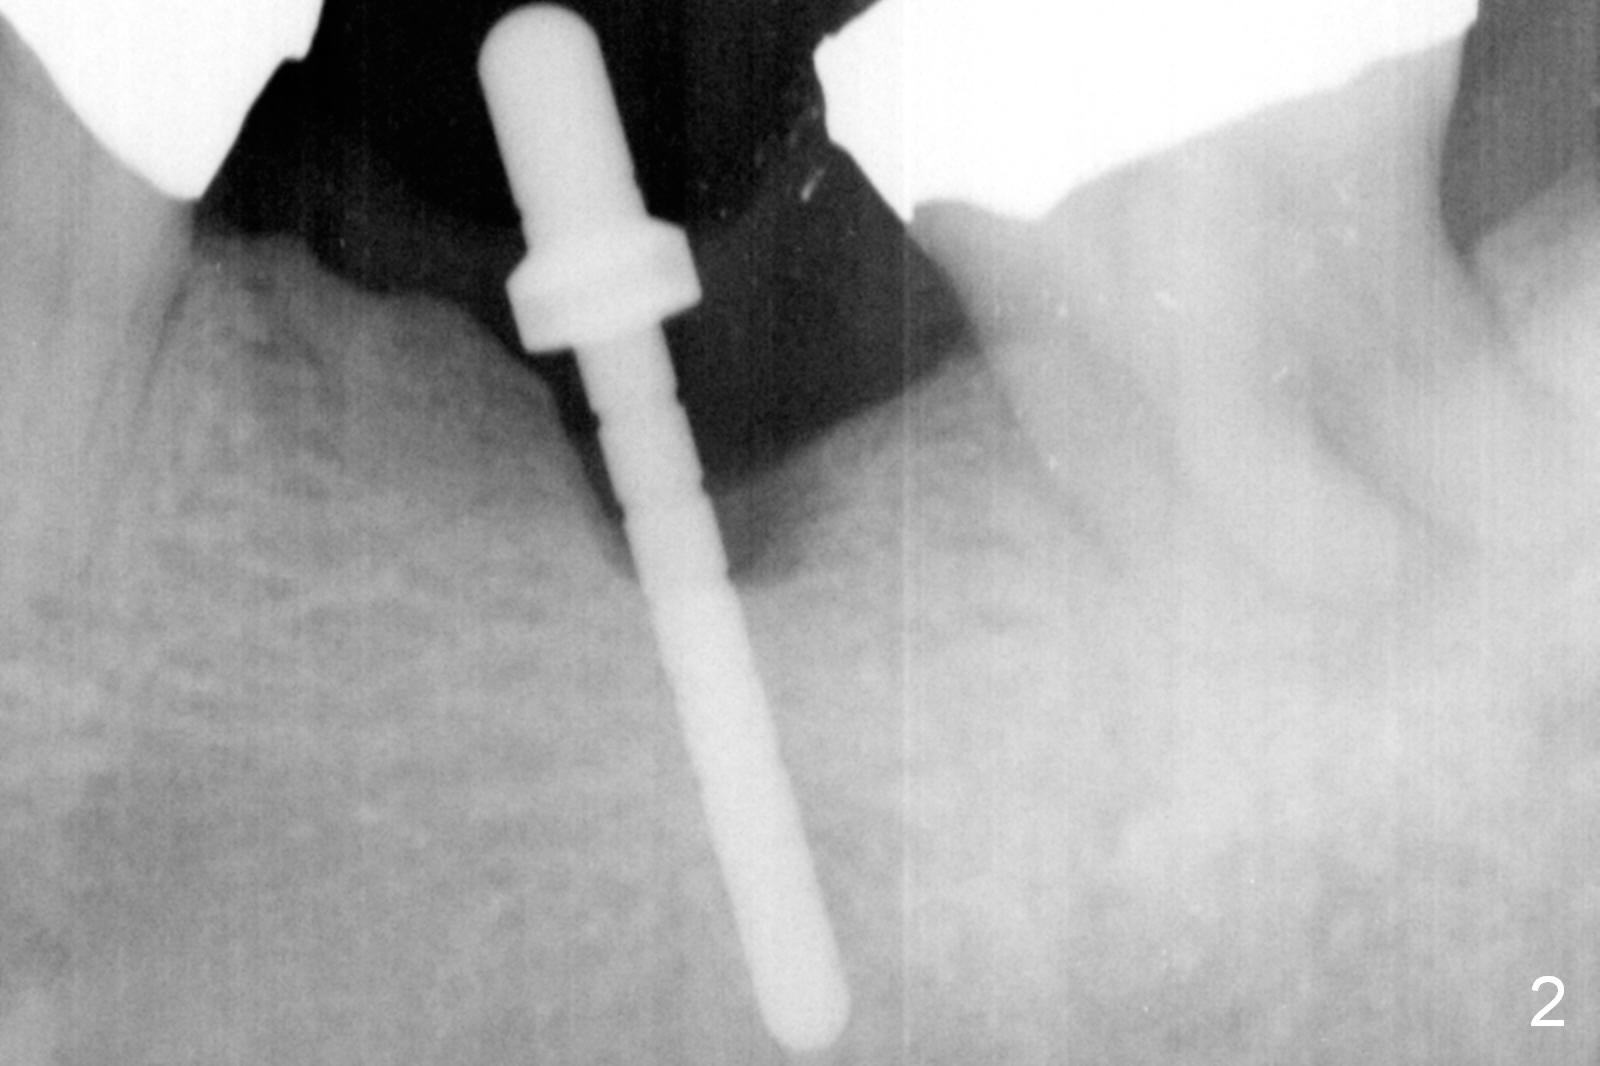

The narrow ridge top is trimmed until the buccolingual width is 7-8 mm; osteotomy starts in the flattened ridge (Fig.1, 2). A 5x10 mm implant is being placed (Fig.3). A cemented abutment (6.5x5.5(5) mm) is placed after adjusting the mesial and distal walls of the trimmed ridge (Fig.4). The patient returns for restoration 6 months postop. The coronal opening of the osteotomy becomes flared (Fig.5). The position and trajectory of the osteotomy should have been changed as early as possible (Fig.6, more or less parallel to the premolar) to avoid necessity of changing the cemented abutment (Fig.7 (* keratinized gingiva)) to an angled one (5.5 x15 degree A (4) mm).